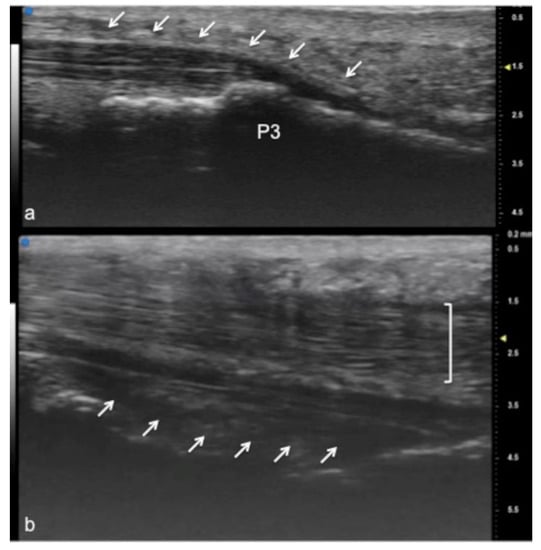

Figure 3.

Flexor tendon of a finger. Using UHFUS at the flexor tendons, the same spatial resolution can be achieved as in the imaging of the extensor tendons. In (a), the sagittal view of the deep flexor tendon component inserting on the basis of the distal phalanx (P3). In (b), the superficial component of the flexor tendon (white arrows) lying near the deep component (white square parenthesis).